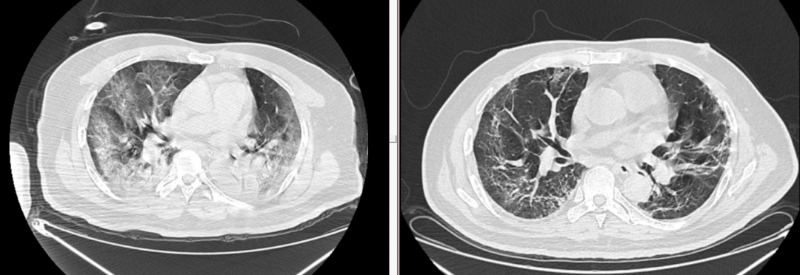

由于患者既往有高血压、糖尿病史,属新冠高危人群,病情发展迅速,胸部CT见肺部浸润面积超过70%,符合“白肺”改变,入院时情况已经非常严重,呼吸窘迫,伴有呼吸衰竭,尽管已气管插管呼吸机辅助呼吸,高浓度吸氧下氧合指数仍然只有80左右,符合新冠感染危重型的标准。此时吴先生的病情只能用“九死一生”来形容。

经过医护人员的及时救治、细心呵护,吴先生成功闯过“感染关”“出血关”“缺氧关”,病情稳定,可自行下床活动,复查胸部CT肺内病灶明显吸收减少,各项指标均达到出院标准,于2023年2月3日顺利出院。

治疗前后胸部CT对比